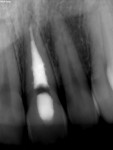

The initial clinical examination showed an intact crown with no caries or restorations present and a vital pulp. However, periapical radiographs revealed a well-defined symmetrical radiolucency, which ballooned out of the pulp chamber (Figure 2). No periapical lesion or widening of the periodontal ligament space was found. The patient had an endodontic consultation, which included an intraoral examination, shifted periapical radiographs, and a CBCT image (Figure 3), to assess the presence and type of resorption. CBCT imaging is crucial in differentiating between internal and external resorption and determining the extent of the lesion, which will affect the treatment plan and outcome.1,5

Electric pulp testing of the maxillary left central incisor was within normal limits, but the tooth exhibited a delayed response to cold. A diagnosis of asymptomatic irreversible pulpitis due to internal resorption with normal apical tissues was established. Two treatment options were presented to the patient: 1) nonsurgical root canal therapy (NSRCT) followed by internal bleaching; or 2) NSRCT with external bleaching. Due to the patient’s young age combined with her history of orthodontics and trauma, NSRCT with external bleaching was chosen to minimize the risk of external root resorption. Also, because of time constraints on the patient, the bleaching process was started prior to completion of root canal therapy.

At the conclusion of phase one, the left central incisor was lighter than the adjacent teeth; therefore, the patient was instructed to use the full-arch tray and apply the bleaching gel to all maxillary teeth and wear the tray overnight for an additional 2 weeks. At the conclusion of phase two a uniform shade was achieved to the patient’s satisfaction (Figure 5 and Figure 6). The NSRCT was completed without any signs of canal wall perforation and the lingual access was restored with Kerr Premise composite resin shade A1 (Figure 7). A 1-year follow-up will be performed.